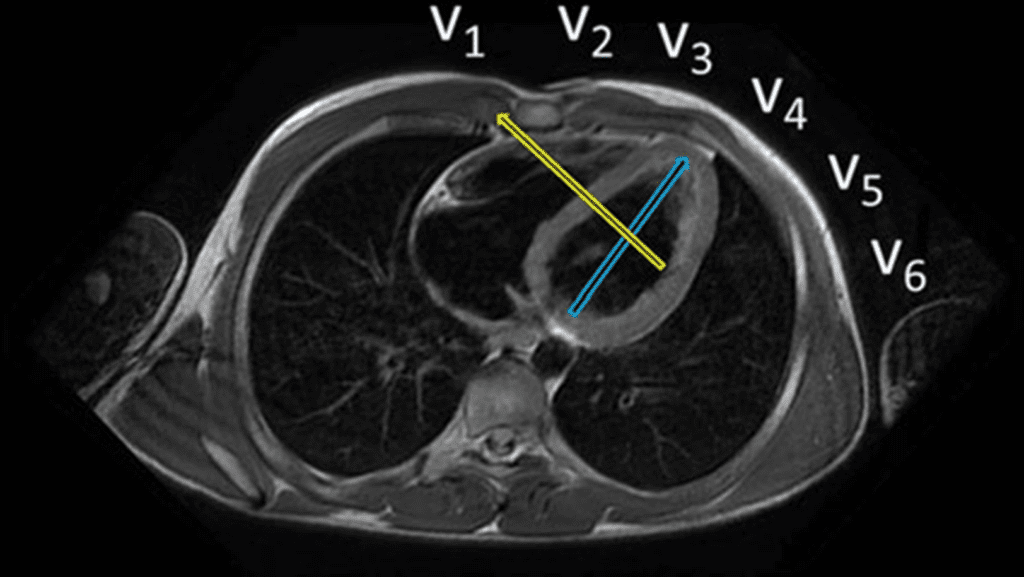

A chamada “parede dorsal” é um dos mitos mais duráveis do ECG. Durante décadas, ensinou-se que certas alterações — especialmente onda R alta em V1–V2 — representariam um infarto da parede posterior (ou dorsal). O problema é que essa parede, do jeito que foi imaginada, praticamente não existe.

O erro nasce de uma premissa anatômica equivocada. O coração não está disposto no tórax como um bloco anterior–posterior. Ele ocupa uma posição oblíqua, e a região antes chamada de “posterior” corresponde, na verdade, ao segmento inferobasal, que faz parte da parede inferior, e não de uma parede independente.

Com o avanço da ressonância magnética cardíaca, esse dogma caiu. Estudos de correlação ECG–RMC mostraram que:

- Onda R aumentada em V1–V2 não indica infarto posterior.

- Esse padrão, quando relacionado a infarto, corresponde mais frequentemente a infarto da parede lateral, cujo vetor de necrose se projeta em direção às derivações direitas.

- Um infarto isolado da suposta “parede posterior” é excepcionalmente raro.

Por isso, a terminologia moderna abandonou o termo “parede posterior/dorsal”. A classificação atual descreve as paredes de forma mais precisa: anterior, septal, lateral e inferior, com seus segmentos basal, médio e apical. O que antes se chamava de “posterior” passou a ser corretamente reconhecido como inferior (inferobasal).

Na prática clínica, insistir no rótulo de parede dorsal gera confusão diagnóstica, interpretações erradas do ECG e comunicação imprecisa entre clínico, hemodinamicista e imagem. Nomear errado é pensar errado.